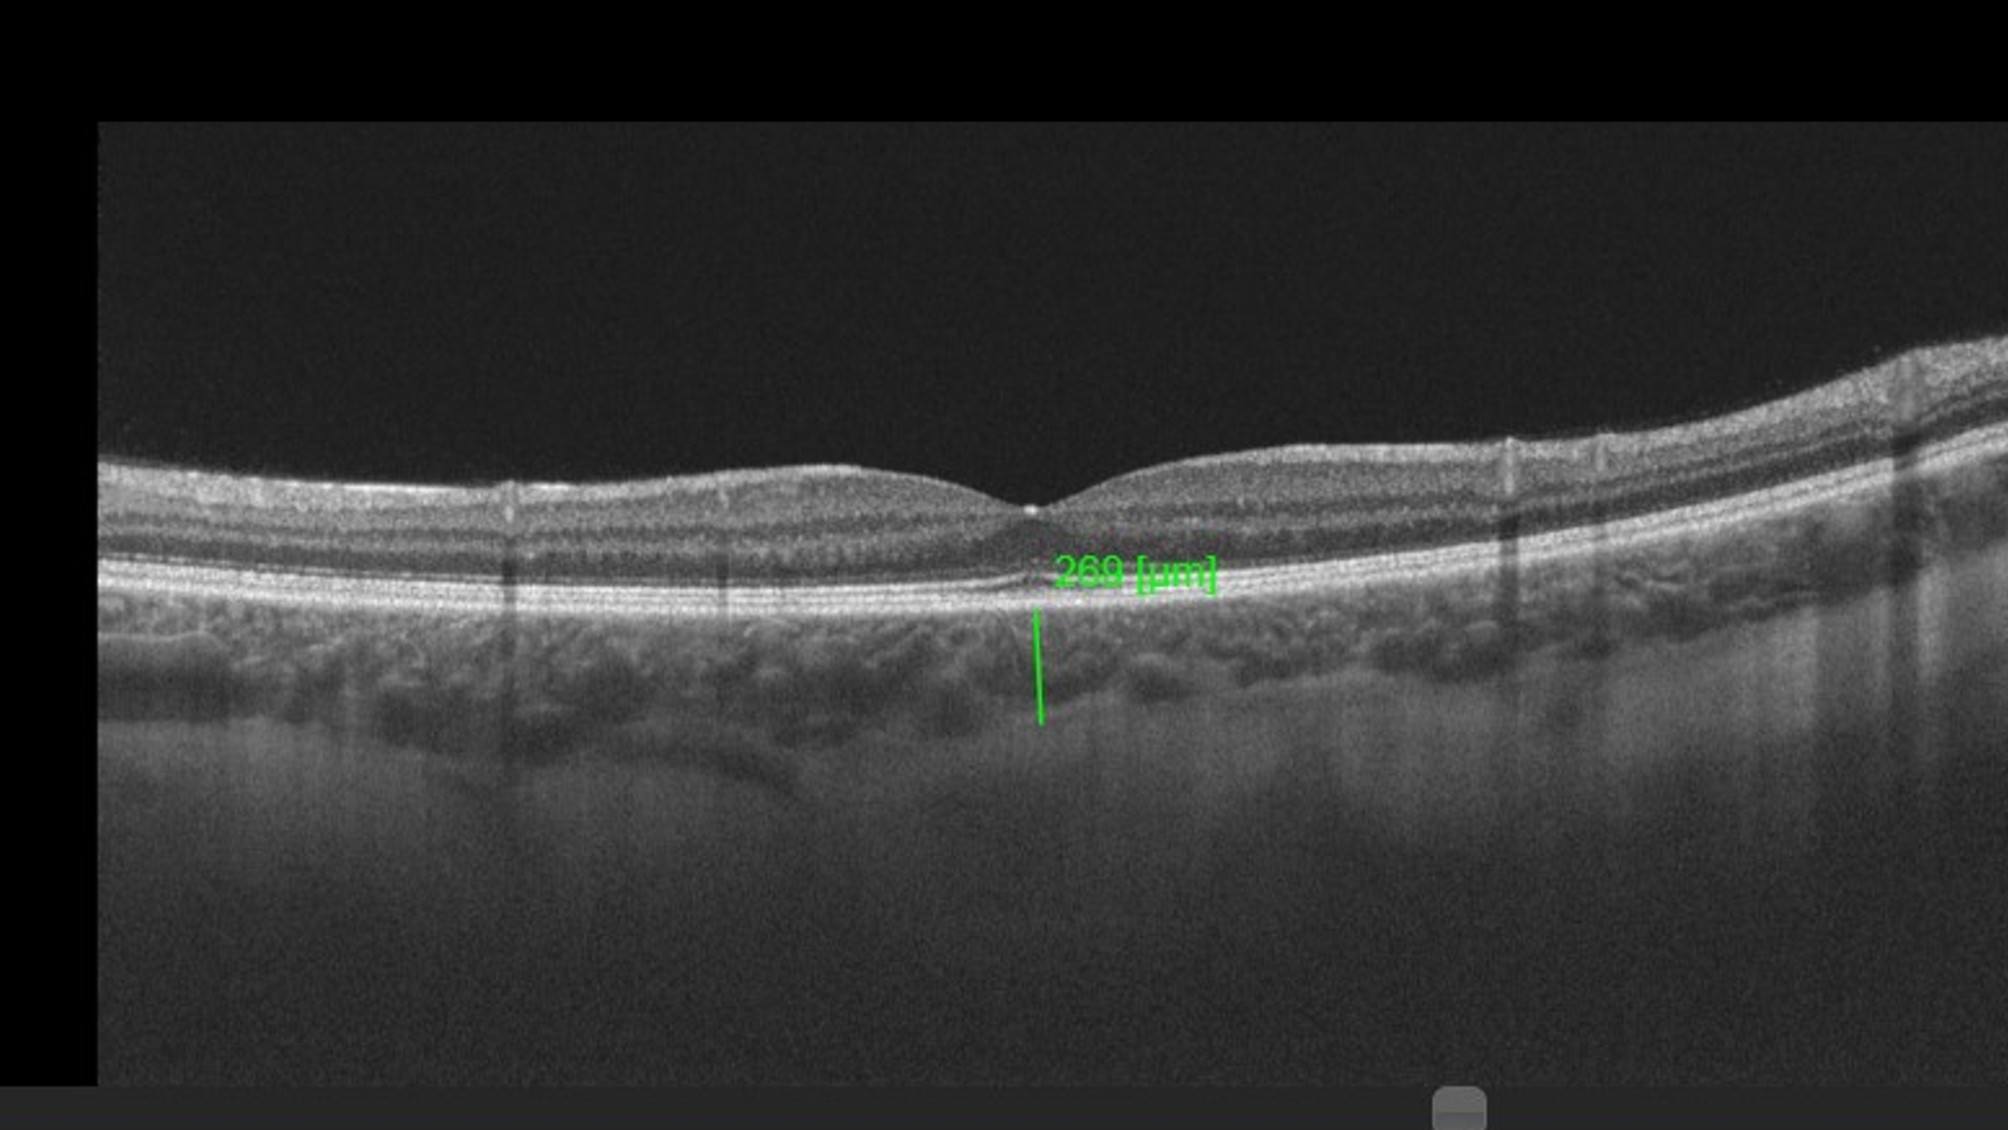

Optical coherence tomographic image of the fovea showing the subfoveal choroidal thickness measurement.